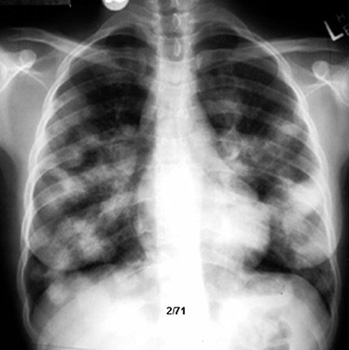

Progression from alveolar pattern to interstitial fibrosis (apparent "radiological improvement", but worsening physiologically)